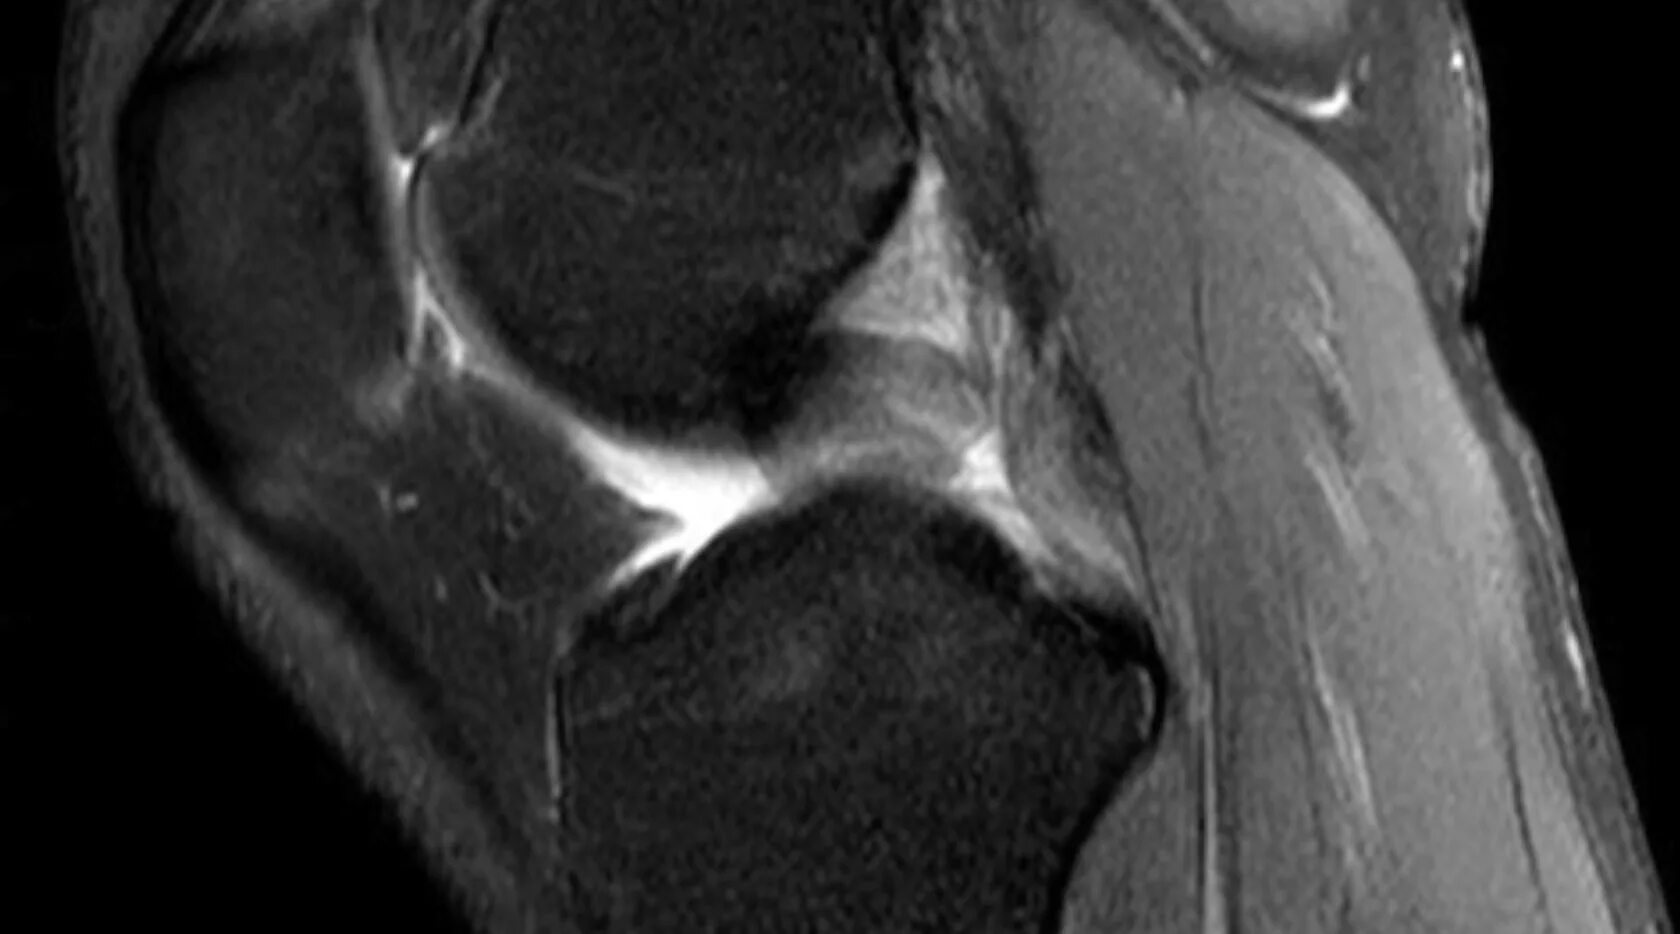

Синовиомы